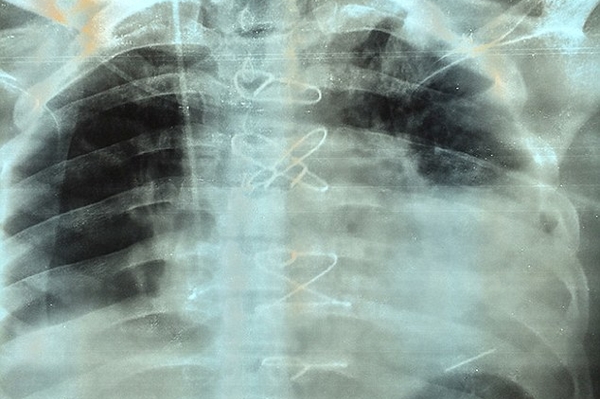

Доктор Анил Джейн, кардиохирург, который руководил операцией, сказал, что это был очень редкий случай, и удивительно, что пациент жил с пулей в сердце в течение двух месяцев: "Пуля находилась в сердечной мышце у верхушки левого желудочка, одной из двух камер сердца. Это уникальный случай, который запросто мог стать фатальным. То, что он прожил два месяца с пулей в таком месте - уникальный случай, это очень счастливый человек"

Во время трехчасовой операции команде из пяти врачей пришлось остановить сердце пациента и поддерживать его с помощью аппарата искусственного кровообращения. Только так они могли извлечь пулю. Оперативное вмешательство прошло успешно и сейчас Бхарат Шарма восстанавливается в отделении интенсивной терапии больницы. Пулю, которая в любой момент могла его убить, он хочет сохранить в качестве напоминания о том, как близко он подошел к смерти.